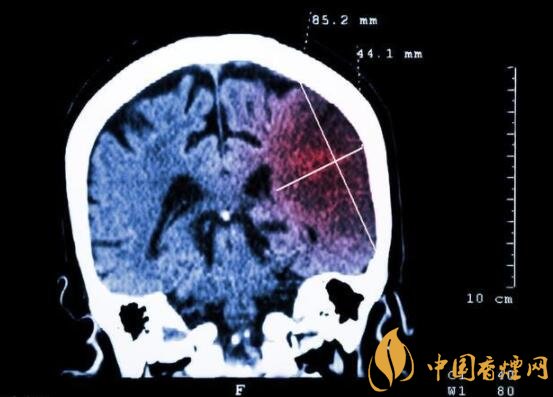

一般而言,急性腦梗塞與長期吸煙有非常密切的聯(lián)系。有長期煙齡遇到肢體活動(dòng)不順,做頭顱核磁共振檢查往往查出一側(cè)大腦中動(dòng)脈閉塞的可能性很高。由此可見,吸煙確實(shí)與中風(fēng)存在一定聯(lián)系。

在這當(dāng)中,吸煙者與不吸煙者做對(duì)比,發(fā)生中風(fēng)時(shí)間可提前十年。按照每日吸煙1-20支,對(duì)比不吸煙者發(fā)生中風(fēng)風(fēng)險(xiǎn)高出3.3倍;每日吸煙20支以上者,比不吸煙者高出5.6倍;30-40歲吸煙者,發(fā)生腦梗塞風(fēng)險(xiǎn)比不吸煙者高出5倍;50-60吸煙者,發(fā)生腦梗塞風(fēng)險(xiǎn)比不吸煙者高出3倍。由此可見,吸煙量越大,吸煙時(shí)間越長,發(fā)生中風(fēng)的可能性越高,特別是多發(fā)生在中年